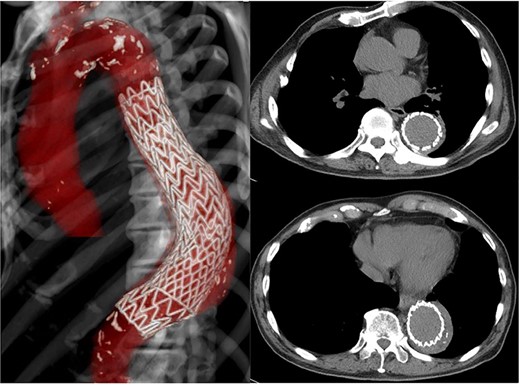

CT 15 months after reconstruction showed regression of the aneurysm, measuring 53 × 53 mm (Fig. 3). He had no further signs of infection.

CT 15 months later shows regression of the aneurysm to 53 mm in diameter.